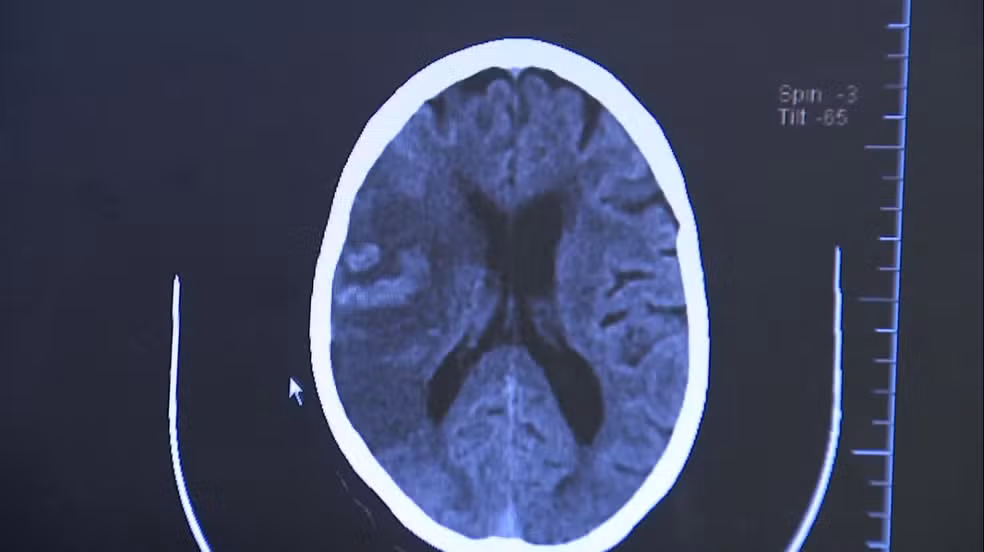

O diagnóstico é feito por tomografia computadorizada ou ressonância magnética do crânio. “Esses exames permitem detectar a área afetada e definir se é um AVC isquêmico ou hemorrágico”, diz Chaddad.